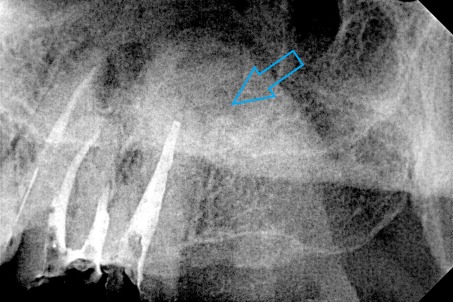

Ο ασθενής παραπονείται για έναν μόνιμο πόνο στην περιοχή του αριστερού ιγμορείου. Ανέφερε οτι πριν χρόνια πραγματοποιήθηκε στον αριστερό γομφίο (τραπεζίτη) μία απονεύρωση. Μετά από καιρό εμφανίστηκαν τα συμπτώματα πόνου, χωρίς καμία βελτίωση. Μετά τον αποκλεισμό της ανάμειξης του ιγμορείου στη εμφάνιση των συμπτωμάτων ακολούθησε η κλινική και ακτινογραφική εξέταση του δοντιού. Η ακτινογραφία αποκάλυψε την ατελή απονεύρωση του δοντιού.

Μετά από συνεννόηση με τον ασθενή αποφασίστηκε η επανάληψη της ενδοδοντικής θεραπείας (απονεύρωσης). Ακολούθως έγινε τοποθέτηση του ελαστικού απομονωτήρα, η διάνοιξη του δοντιού και η αφαίρεση του παλιού εμφρακτικού υλικού από τις ρίζες.Επιπρόσθετα εντοπίστηκε και παρασκευάστηκε και 4ος ριζικός σωλήνας, ο οποίος δεν είχε επεξεργστεί στην πρώτη ενδοδοντική θεραπεία ( απονεύρωση ) του ασθενούς.

Διαπιστώθηκε η ενσβεστίωση 2 ριζικών σωλήνων του δοντιού (ριζών), κάτι που δεν επέτρεψε την επεξεργασία του δοντιού σε όλο το μήκος αυτών των ριζών. Παρολ΄ αυτά μετά τη δεύτερη συνεδρία ο ασθενής ανέφερε την ανακούφιση και την εξάλειψη των συμπτωμάτων, που τον ταλαιπωρούσαν τα τελευταία χρόνια.

Εφόσον το δόντι ήταν ασυμπτωματικό και ο ασθενής δεν αισθανόταν πλέον πόνο ολοκληρώθηκε η διαδικασία της απονεύρωσης με τη χρήση των μηχανοκίνητων εργαλείων και την τελική έμφραξη των ριζών του δοντιού με νέο εμφρακτικό υλικό.

ΠΡΙΝ

ΜΕΤΑ